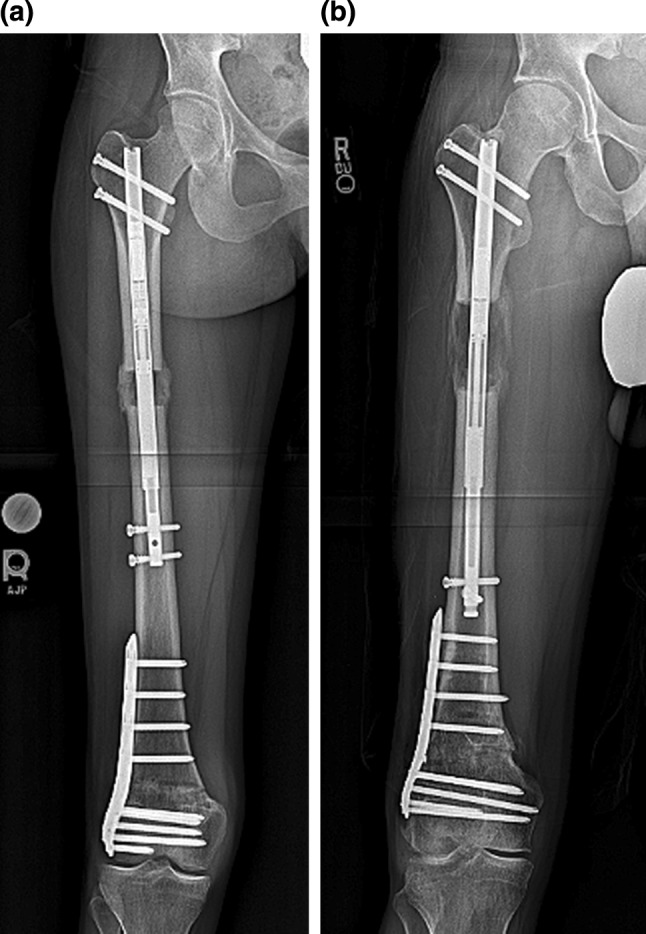

Fig. 7.

a This post-operative radiograph of patient 1 shows a consolidating proximal regenerate with bicortical bridging callus during the consolidation phase of lengthening, b this post-operative X ray of patient 3 shows a healthy regenerate during the distraction phase of lengthening. The rate of distraction was not altered after this appointment